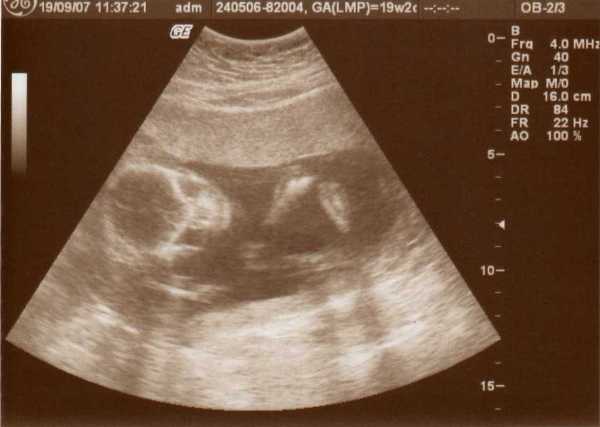

Üdv az újaknak! Itt valóban nagyon parás kismamák vannak, én az első 12 hetet végigparáztam, utána már csak mértékkel, de amióta mozog a bébi, meg láttam 4D-n, azóta oltári nyugodt vagyok...

Délután megyek a dokimhoz, terhesgondozásra, most kapok időpontot a következő UH-ra. Szerintem két hét múlva megyek, mert jövő héten sulihetem lesz, úgyhogy az kilőve. De most annyira nem is sürget a dolog, mivel a múlt héten volt a 4D.

Én is ajánlom mindenkinek a 4D-t, mi is nagyon jó helyet fogtunk ki, de mi vidéken, Szombathelyen voltunk, az van közel.

Egyébként mint megtudtam, ez a rendelő a Telki Magánkórház partnerintézete. Mondjuk elég luxus szinten mennek a dolgok, az biztos. De főleg az volt jó, hogy a szonográfus nő tök profi volt, és nagyon jól elmondott mindent, szinte minden részét láthattuk a kis kincsünknek, és még a nemét is megtudtuk kb. 9 perc után.

Szóval én nagyon meg voltam elégedve a szolgáltatással, egyébként 20 perces vizsgálat volt, szívhangot kihangosították, minden részét alaposan megnézték, kaptunk DVD-t, meg postán kapunk fényképeket. És ez volt 12.000 Ft.